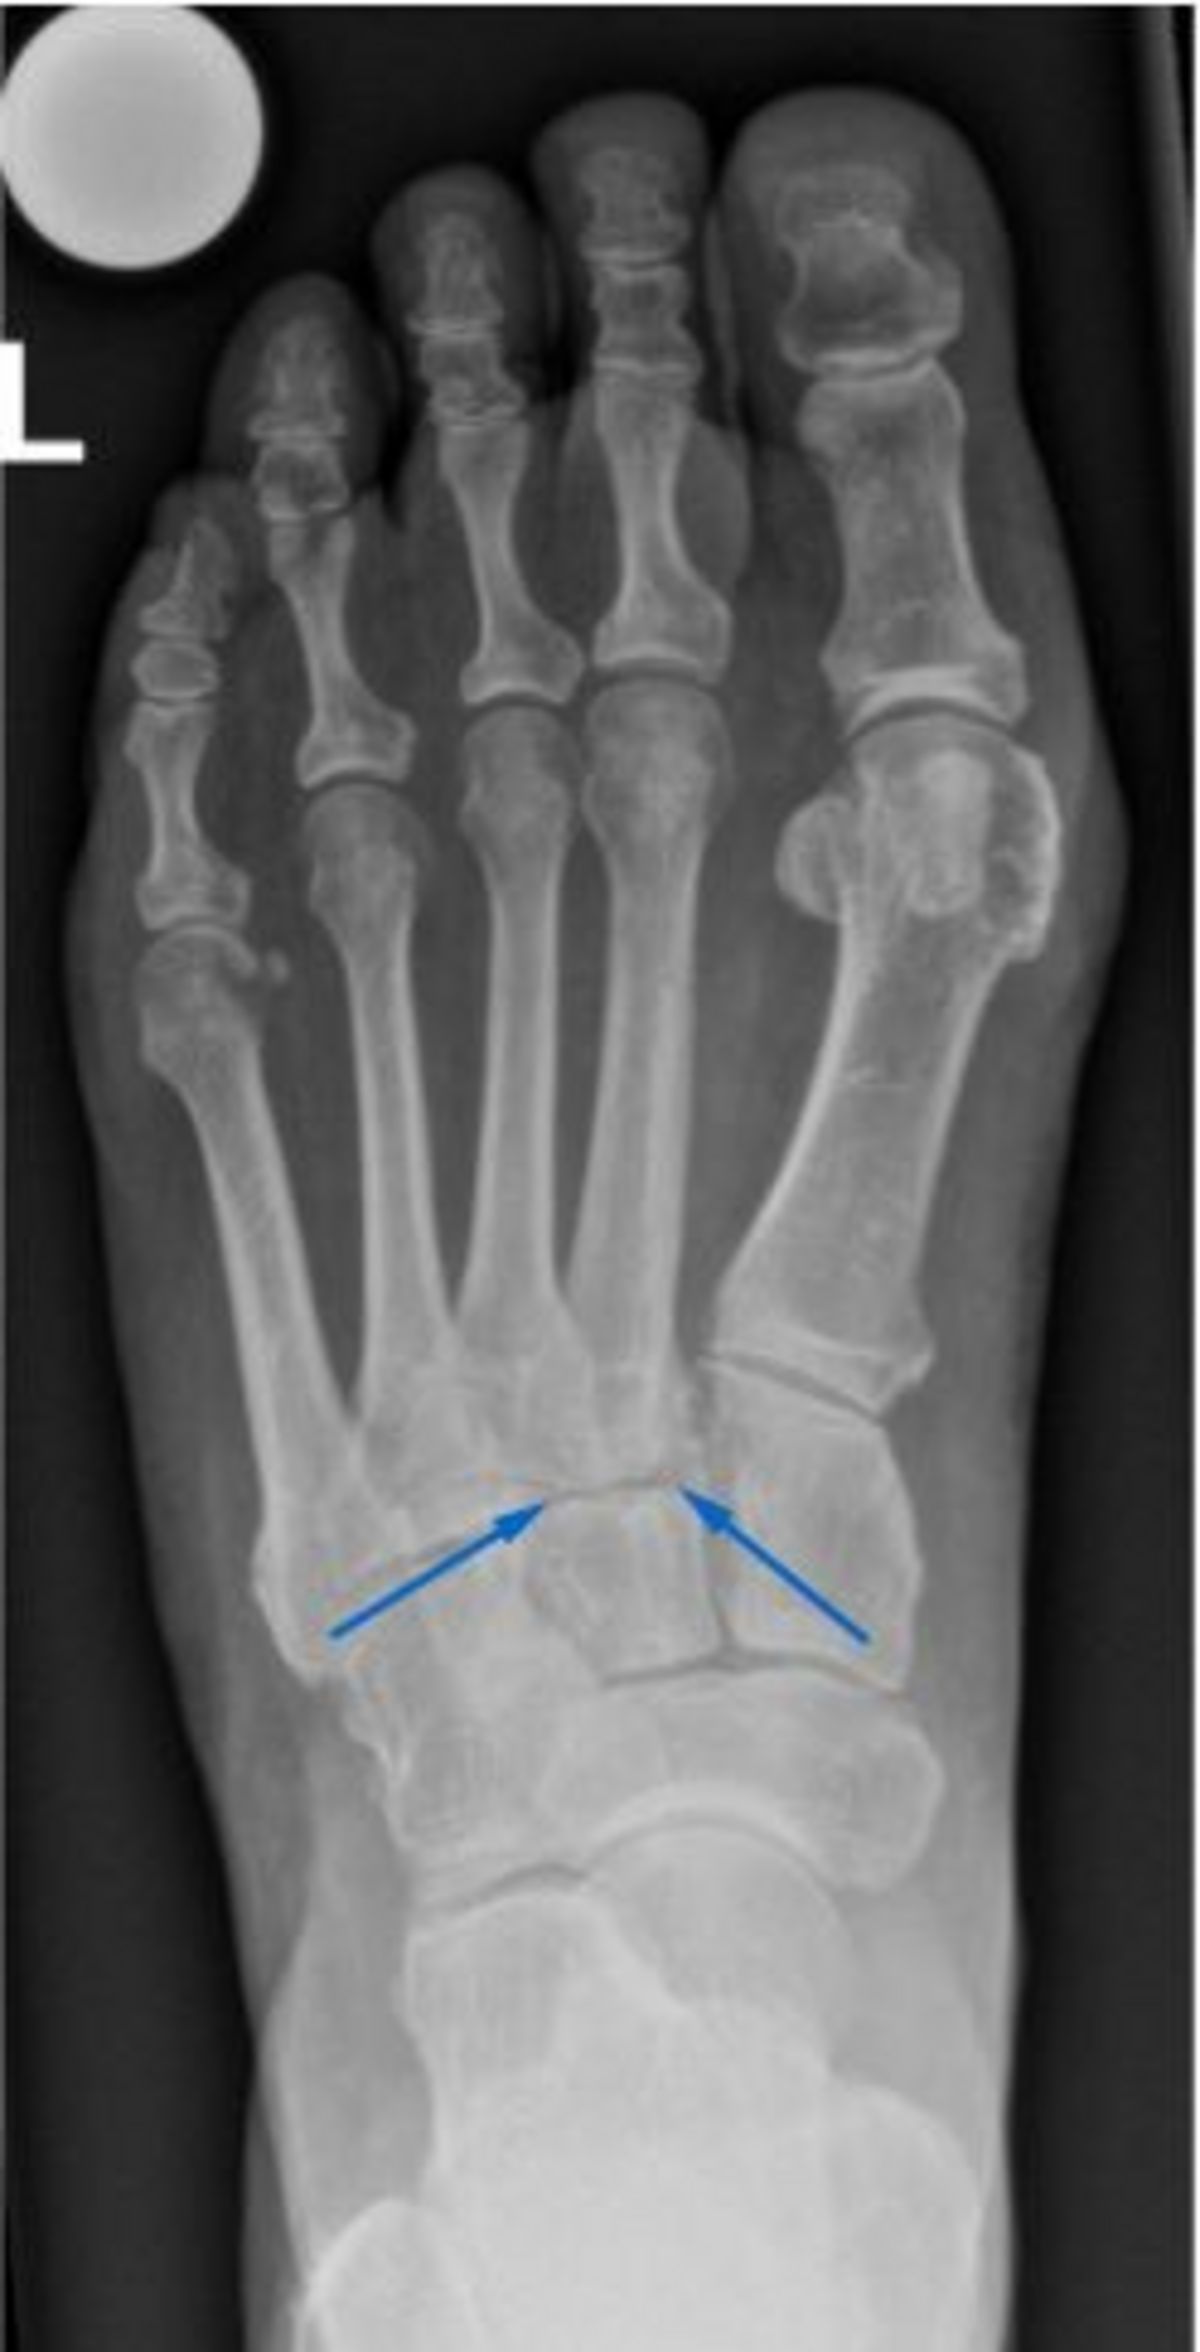

Röntgenbilder sind zur Diagnosestellung hilfreich. Zum einen zeigen sie meist bereits die Arthrose der Gelenke, zum anderen kann ihre Stabilität beurteilt werden. Aufgrund der Form des Fussgewölbes sind Röntgenbilder mehrerer Ebenen notwendig, um eine zuverlässige Aussage treffen zu können. Unter Umständen ist zusätzlich eine Magnetresonanztomographie (MRT bzw. engl. MRI für magnetic resonance imaging) nötig, um das genaue Ausmass der Arthrose und Verletzung des Mittelfusses bestimmen zu können.

Die Mittelfussarthrose kann nach einer Verletzung (posttraumatisch) oder durch Verschleiss (degenerativ) entstehen. Bei einer Verletzung des Mittelfusses können die Gelenke oder die Bänder, die für ihre Stabilität sorgen, geschädigt werden. Dadurch werden die Gelenke falsch belastet und es kann mit der Zeit zu einem frühzeitigen Verschleiss (Arthrose) kommen. Eine Fehlbelastung aufgrund einer Fehlstellung, z. B. bei einem Knicksenkfuss, kann ebenfalls die Arthrose begünstigen. Weitere Ursachen sind rheumatologische oder neurologische Erkrankungen oder eine Überlastung nach einer Rückfussversteifung.

In der klinischen Untersuchung werden Knochenanbauten gesehen und ertastet. Der Schmerz kann zudem durch eine behutsame Belastung des Mittelfusses ausgelöst werden *. Dabei wird der Fuss dosiert gegen den Rückfuss nach aussen gedrückt und verdreht.